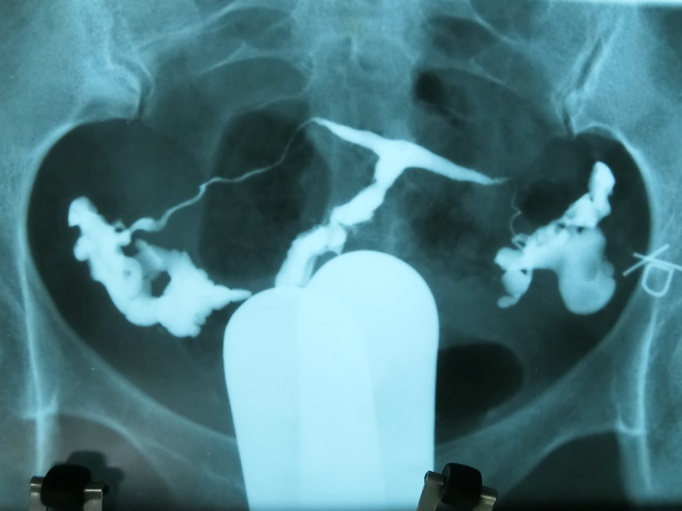

T型子宫有先天性和获得性之分,先天性是指患者胎儿期苯甲酸雌二醇(diethylstilbestrol,DES)宫内暴露或其他因素导致的先天畸形,成因为周边肌肉肥厚,致子宫腔近心端狭窄,中下段侧壁靠近,宫底可略内突,整个宫腔呈“ T ” 型外观(图1),宫体和宫颈长度比2:1。可导致不孕,反复流产,异位妊娠,宫颈机能不全,早产和围产儿死亡。获得性为宫腔粘连后、纤维瘢痕组织的形成,扭曲、塞满或闭锁宫腔,致其宫腔形态酷似“ T ”形,宫腔粘连的组织结构复杂,其边缘不规整,欠规则(图2),获得性T型子宫也与生殖道结核和子宫腺肌症相关,常导致不孕、复发性流产(recurrent pregnancy loss,RPL)和反复种植失败(repeated implantation failure,RIF)。

图1 先天性T型子宫HSG图片